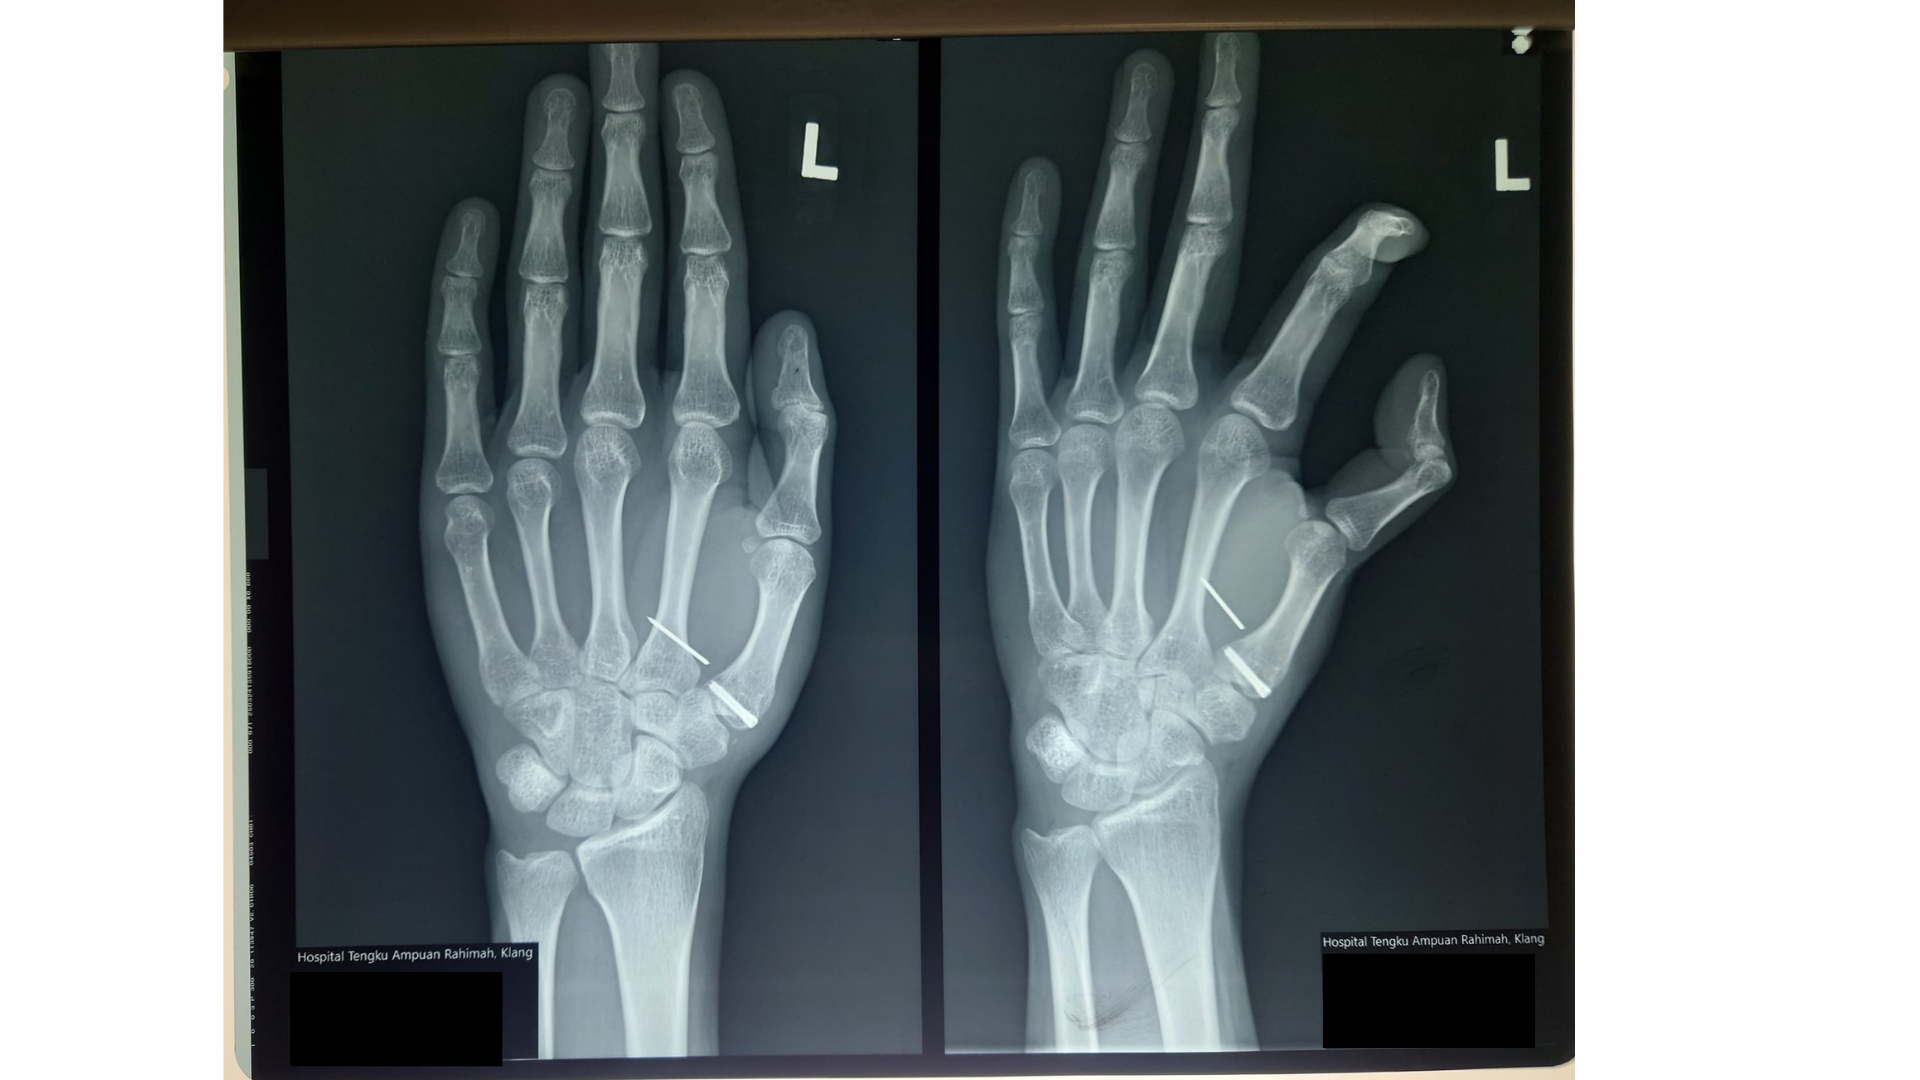

Four years ago, my son John injured his left thumb, which required surgery. A screw and pin were placed in his palm. However,durinng the 1st week of May 2025 he began experiencing a sudden sharp pain. When we brought him to the hospital, an X-ray revealed that one of the pins had become dislodged, causing him to lose the ability to use his left hand. I immediately submitted a prayer request, trusting the Lord for healing. John was admitted and scheduled for surgery but unexpectedly, he contracted chickenpox, and the surgery had to be postponed.

While waiting for the second appointment, something miraculous happened: the very next day, the pin surfaced and came out of his palm on its own! There was no blood, no complications, it came out clean, and the skin healed quickly. No surgery was needed. No medication was required. And best of all, he could use his hand immediately! We give all glory to our Great Physician, Jesus Christ, who performed a divine surgery that no human hands could. Truly, nothing is impossible for our God. Hallelujah!